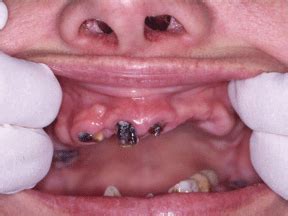

But the damage doesn't stop there. Meth use can also cause a condition known as meth mouth, which is characterized by severe tooth decay, gum disease, and tooth loss. Many meth users experience rapid deterioration of their teeth and gums, to the point where they become virtually unrecognizable.

Meth use has a significant impact on oral health, causing a condition known as “meth mouth.” Meth mouth is characterized by severe dental problems, including tooth decay, gum disease, and tooth loss. The damage to teeth caused by meth use is often irreversible and can lead to life-long dental problems.

The use of meth can cause a range of dental problems, including tooth decay, gum disease, and tooth loss. These issues are often referred to as meth mouth, a term used to describe the extensive damage that methamphetamine can cause to a person's teeth and gums.

Meth use can cause severe dental problems known as meth mouth. Methamphetamine is acidic and can erode tooth enamel, leading to cavities and tooth decay. The drug also causes dry mouth, which decreases saliva production and leads to further tooth decay and gum disease. Additionally, meth users often grind their teeth and clench their jaws, leading to cracked teeth, chipped teeth, and jaw pain.